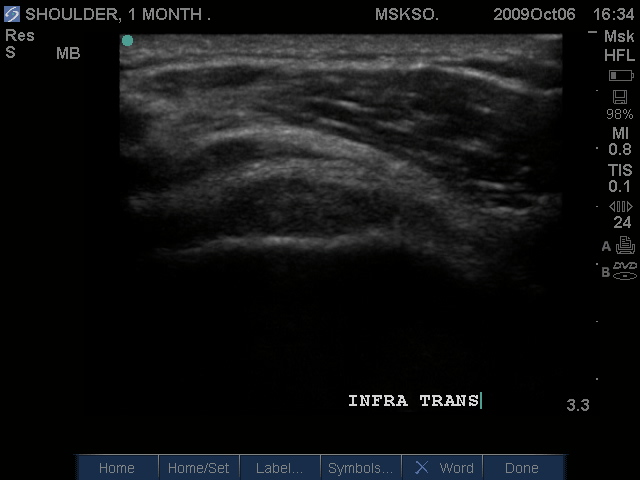

Posteriorly the Infraspinatus tendon in transverse plane is intact, but shows a bursitis that can be traced over the greater tuberosity. Proximal to this site this may be a normal myotendinous junction appearance.